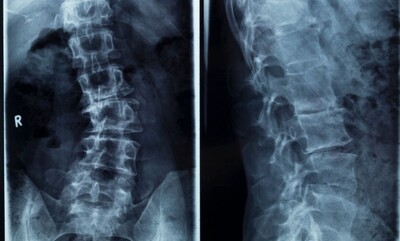

2. Disc Buldges or Herniations

When a disc bulges, a muscle spasms, or a joint inflames, the nearby nerves can get compressed or irritated.

It’s not always a “herniated disc” — sometimes simple inflammation or misalignment is enough to pinch the nerve roots. Identifying the exact source makes a big difference in how quickly symptoms calm down.